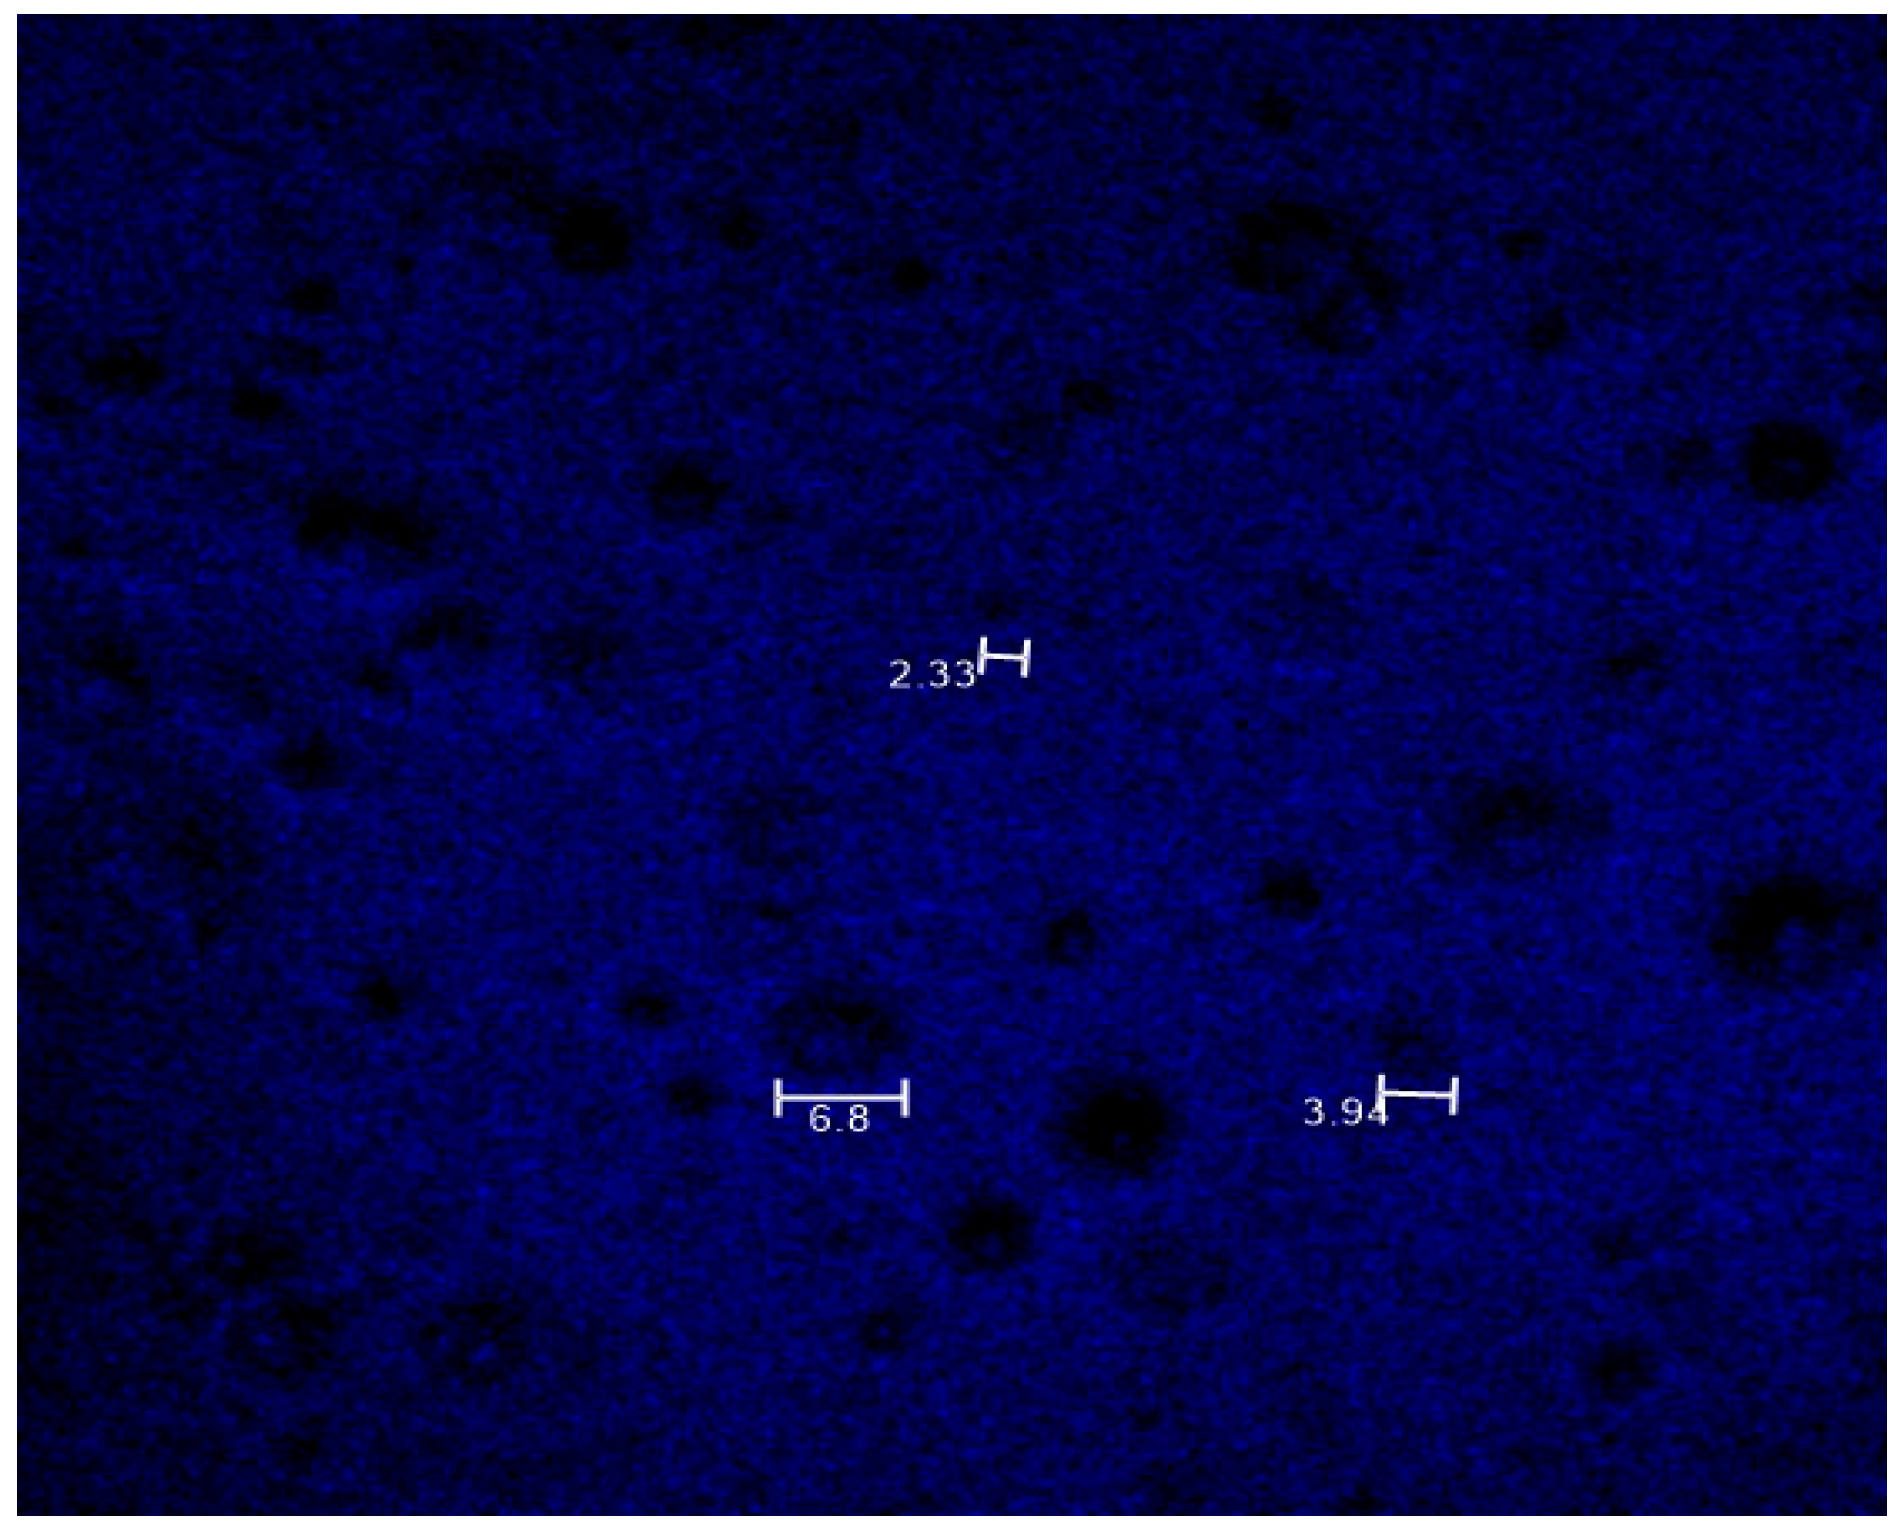

3.5. Drug Distribution Analysis